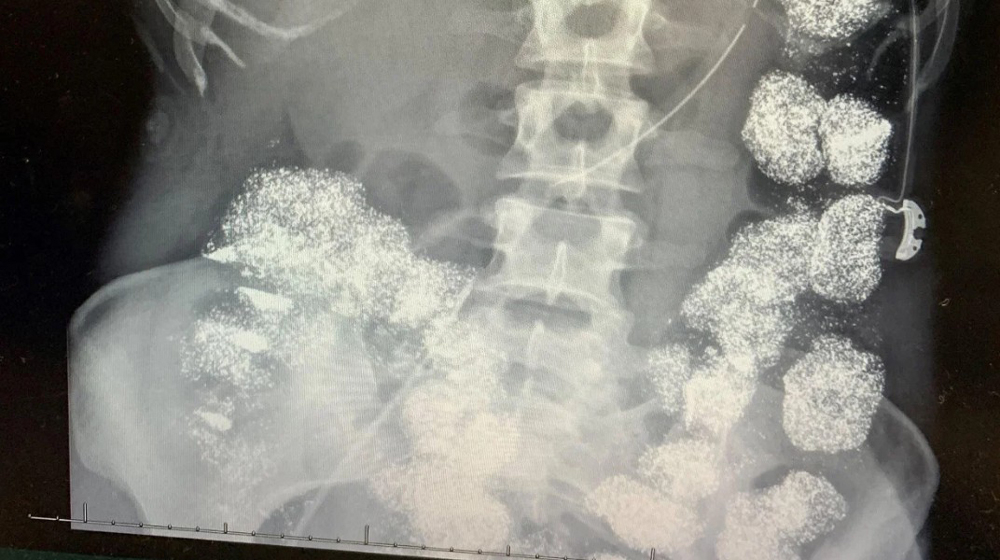

Kết quả xét nghiệm cho thấy nồng độ chì trong máu Pettey vượt mức 80 mcg/dL, gấp 8 lần ngưỡng an toàn. Phim chụp X-quang ghi nhận kim loại nặng lấp đầy đại tràng và dạ dày, thậm chí xâm nhập vào xương. Các bác sĩ nhận định bệnh nhân không thể vô tình nuốt lượng chì lớn như vậy nên lập tức báo cảnh sát điều tra người thân.